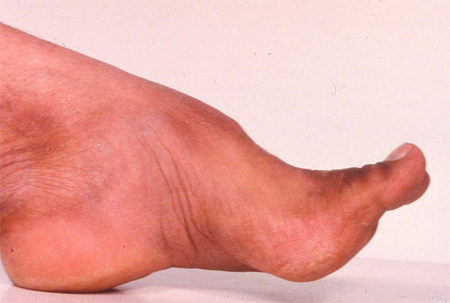

Deformidade de pés cavos na ataxia de Friedreich

Do acervo de Dr. S. H. Subramony; usado com permissão